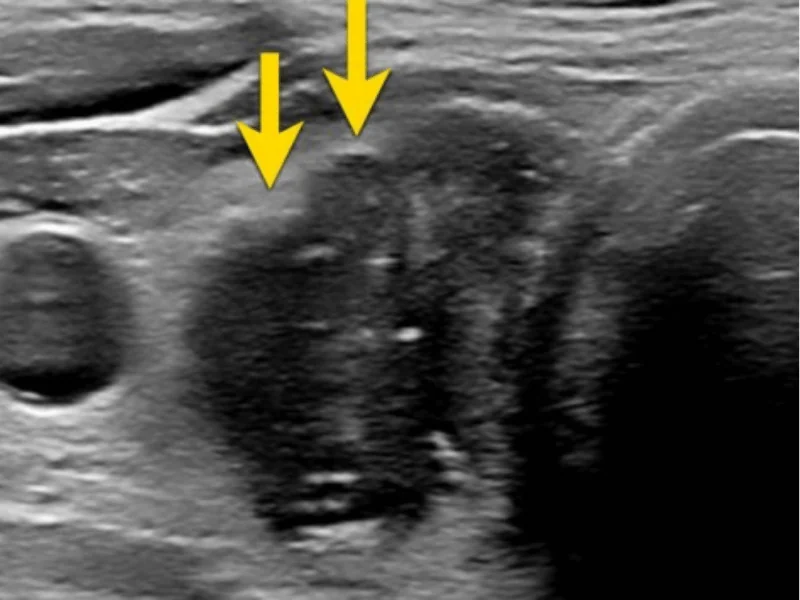

Você recebeu o diagnóstico de um nódulo na tireoide e não sabe por onde começar? 🤔 Não se preocupe, estamos aqui para esclarecer todas as suas dúvidas! Neste vídeo, vamos explicar detalhadamente o que é um nódulo tireoidiano, quais são as possíveis causas e, principalmente, quais são os próximos passos que você deve tomar. Abordaremos os exames necessários 🩺, como ultrassom e punção aspirativa por agulha fina (PAAF), para determinar se o nódulo é benigno ou maligno. Falaremos sobre os diferentes tipos de tratamento, desde o acompanhamento médico até a necessidade de cirurgia. 🏥 Além disso, daremos dicas valiosas sobre como lidar com a ansiedade durante esse período e a importância de manter um diálogo aberto com seu médico. 💬 Não deixe que o medo ou a incerteza tomem conta! Assista até o final e sinta-se mais confiante para tomar as melhores decisões para a sua saúde. 💙 📢 Inscreva-se no canal e ative as notificações 🔔 para receber mais conteúdos informativos sobre saúde e bem-estar! ▶Dr. Jônatas Catunda Cirurgião de cabeça e pescoço CRM 14951 RQE 8522 ▶Whatsapp - 85 98107.2268 ▶Consulta online - https://drjonatascatunda.com/consultaonline ▶Esse canal é meramente educacional. Não deve ser utilizado para realizar autodiagnóstico ou auto tratamento!